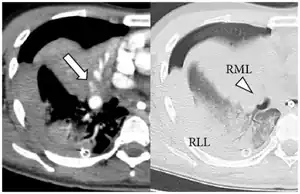

| Extravasation of contrast medium in right middle lobe and compression of middle lobe bronchus by a pulmonary hematoma | |

A pulmonary hematoma is a collection of blood within the tissue of the lung. It may result when a pulmonary laceration fills with blood.[1] A lung laceration filled with air is called a pneumatocele.[1] In some cases, both pneumatoceles and hematomas exist in the same injured lung.[2] Pulmonary hematomas take longer to heal than simple pneumatoceles and commonly leave the lungs scarred.[1] A pulmonary contusion is another cause of bleeding within the lung tissue, but these result from microhemorrhages, multiple small bleeds, and the bleeding is not a discrete mass but rather occurs within the lung tissue. An indication of more severe damage to the lung than pulmonary contusion, a hematoma also takes longer to clear.[3] Unlike contusions, hematomas do not usually interfere with gas exchange in the lung, but they do increase the risk of infection and abscess formation.[4]